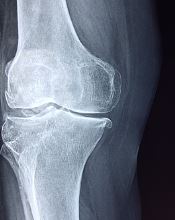

무릎 연골이 손상된 경우에는다양한 증상을 유발하며 불편함과 삶의 질에 영향을 미칠 수 있습니다. 효과적인 관리와 회복을 위해서는 이러한 증상과 해결책을 이해하는 것이 중요합니다.

이러한 방법으로도 증상이 회복되지 않는다면 반드시 의사 등 전문가에게 찾아가서 치료를 받아야 합니다. 그렇다면 어떤 증상이 나타날까요? 오늘은 무릎 연골 손상 증상 알아보겠습니다.

무릎 연골 손상 증상